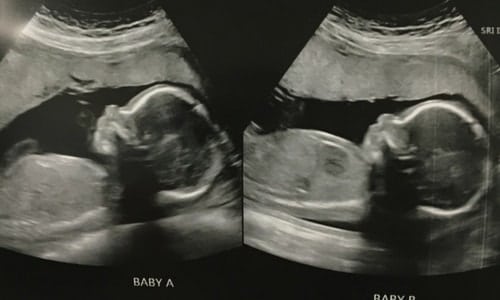

Before my husband and I knew we were having twins, we weren’t going to find out the gender. Now that there are twins on the way I feel like we should, but we are having such a tough time deciding. Does anyone have any insight into this?

We found out. Similar thinking as you! Had it been one we were in for a surprise! But twins was a sweet surprise enough! We simply couldn’t wait to find out what they were. I feel I connected with the fetuses more after I knew what they were and had a clearer idea of what their relationship with each other would be like. Boy/girl. It was one of my sweetest experiences to share with my husband at our ultrasound.